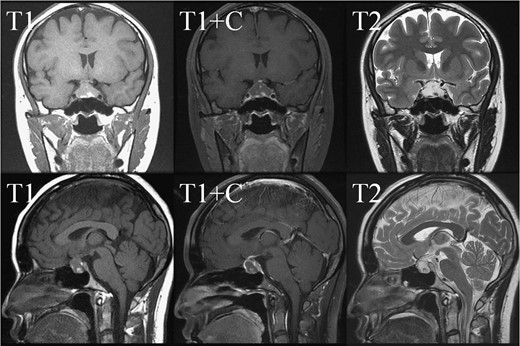

In May 2018, a 28-year-old woman with medical history of sick sinus syndrome and mitral valve prolapse, who just gave birth to a child in April 2018 coming to our Emergency Department with the chief complaint of severe headache and blurred vision for one week. At the Emergency Department, her visual acuity was 0.1 on her right eye and 0.9 on her left eye. Brain CT (computed tomography) scan was checked showing increased soft tissue density over sellar and suprasellar regions, more on the right side. Sellar MRI (magnetic resonance imaging) (Fig. 1) was further arranged which showed a mass with rim enhancement about 2.2 cm ×1.4 cm ×1.2 cm in size located at sella with suprasellar extension with several suspected hemorrhagic foci inside. Under the impression of pituitary apoplexy, she was admitted for further evaluation and management. On admission, her neurological examination showed essentially negative findings except declined right visual acuity; her hormone study showed low level of cortisol (cortisol<1.00 μg/dL) and others were within normal limits. Before surgery, ophthalmologist was consulted again to repeat her ophthalmological examination. The visual acuity of her right eye and left eye improved to 0.8 and 1.0 respectively after the use of steroid. The visual field test showed peripheral defect over the upper visual field of both eyes. Under general anesthesia, she underwent endoscopic endonasal transsphenoidal approach with the removal of tumor and skull base reconstruction. Grossly, the tumor was yellow and soft in consistency and at the end of the procedure, the pituitary gland was well exposed and visible (Fig. 2). After surgery, her vision was subjectively improved; her cortisol level returned to normal (cortisol=16.6ug/dL) and other hormonal data were within normal limits. Histology examination of the tumor (Fig. 3) showed that it composed of spindle to epithelioid cells forming poorly defined lobules and interlacing fascicles, both featuring eosinophilic and oncocytic cytoplasm, with mild nuclear atypia. Immunohistochemically, the neoplastic cells showed TTF-1(+), GFAP(-), EMA(+) Annexin A1(+), and PAS/DPAS(-). Based on the result of histopathology findings and immunohistochemical stains, spindle cell oncocytoma was diagnosed. Before discharge home, her early post-operative sellar MRI (Fig. 4) showed neither residual nor recurrent lesion; she was discharged in a good condition.

Early post-operative sellar MRI. The coronal view (upper row) and sagittal view (lower row) showing the status post removal of the tumor over the sellar and suprasellar regions with poor-enhancing area at the posterior sellar region which favored postoperative change.